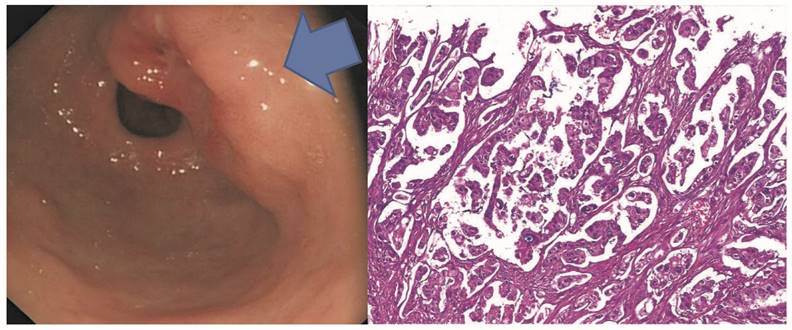

Figure 2

Representative micropapillary early gastric adenocarcinoma in the gastric antrum with the endoscopic O-IIA/O-IIC grow patterns in A. Microscopically, the tumor shows micropapillary features without fibrovascular cores but demonstrates empty spaces surrounding each tumor micropapilae.